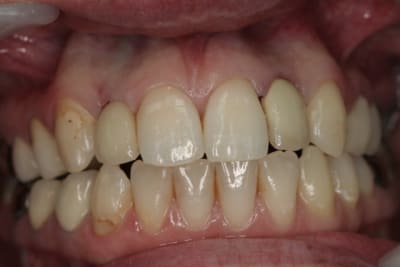

photos finish!!!

à noter...avec le flash...difficile de rendre le "naturel" de ces restaurations(teintes très claires)...après petite gingivoplastie pour harmoniser la hauteur des collets...(surtout pour 12...)

01/09/2010 à 16h54

-1 ou 2 mois plus tard ( je sais plus)

- empreinte avec transfert pop in

- pilier zircone esthétique Axiom

- prothèse et pilier

- pilier zircone en place

- couronne en place (petite compression gingivale)

fin du traitement